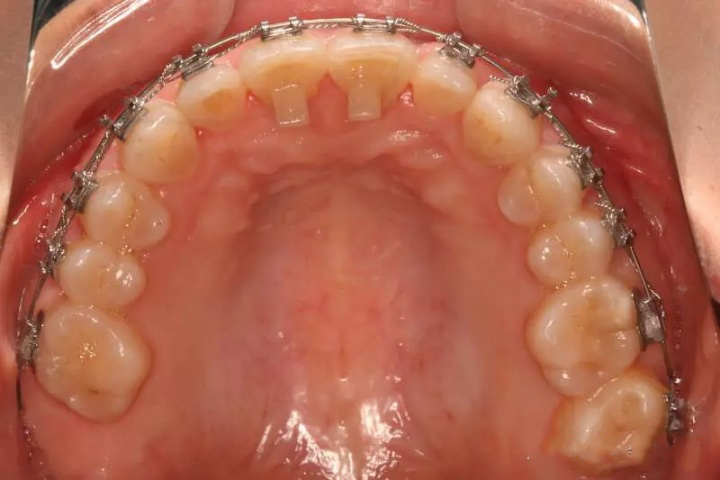

不同于普通口腔诊所,这里采用“正畸-种植-修复”三位一体模式。特别要说的是他们的iTero口扫设备,能模拟不同矫正方案的效果动画,让患者在矫正前就能看到自己牙齿的变化趋势。对于纠结要不要戴牙套的朋友,这种可视化方案确实很加分。

初次戴牙套的3-7天会有酸胀感,但远没到“痛”的程度。美莱采用的自锁托槽摩擦力更小,复诊时医生还会调整加力幅度,多数患者反馈完全在可承受范围。